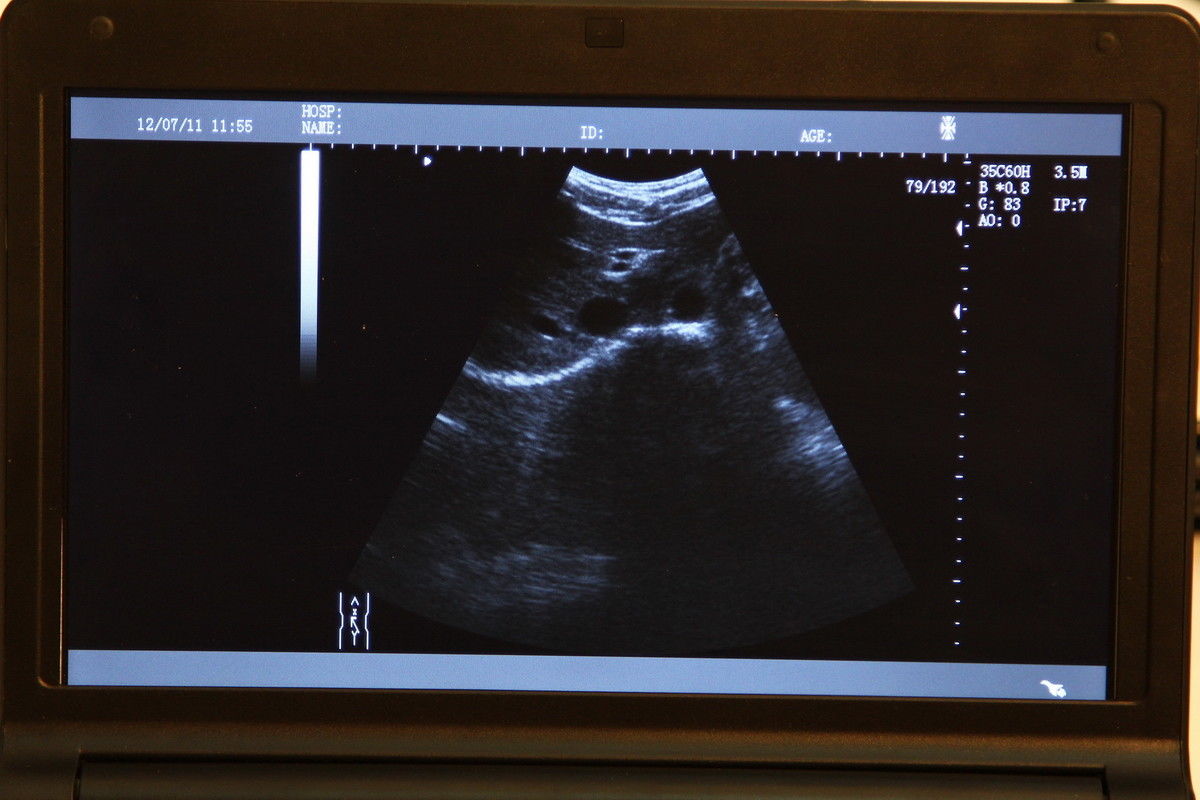

The CE Digital Laptop Ultrasound Scanner is designed to provide high-quality imaging for medical professionals. With its advanced 7.5MHz linear probe, this scanner captures clear and precise images, allowing for accurate diagnostics. It is especially beneficial for procedures requiring detailed visualization, such as vascular and musculoskeletal examinations. This tool empowers healthcare providers, so they can deliver better patient care through enhanced imaging technology.